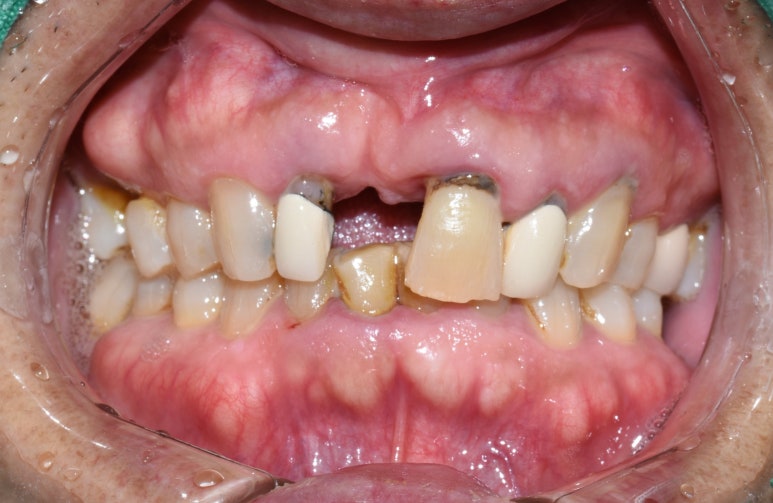

전후를 다시한번 비교해 볼까요?

가장 많이 보이는 두 앞니가 제대로 되면서

웃을 때 치아가 많이 환해보이는 효과가 나타납니다.